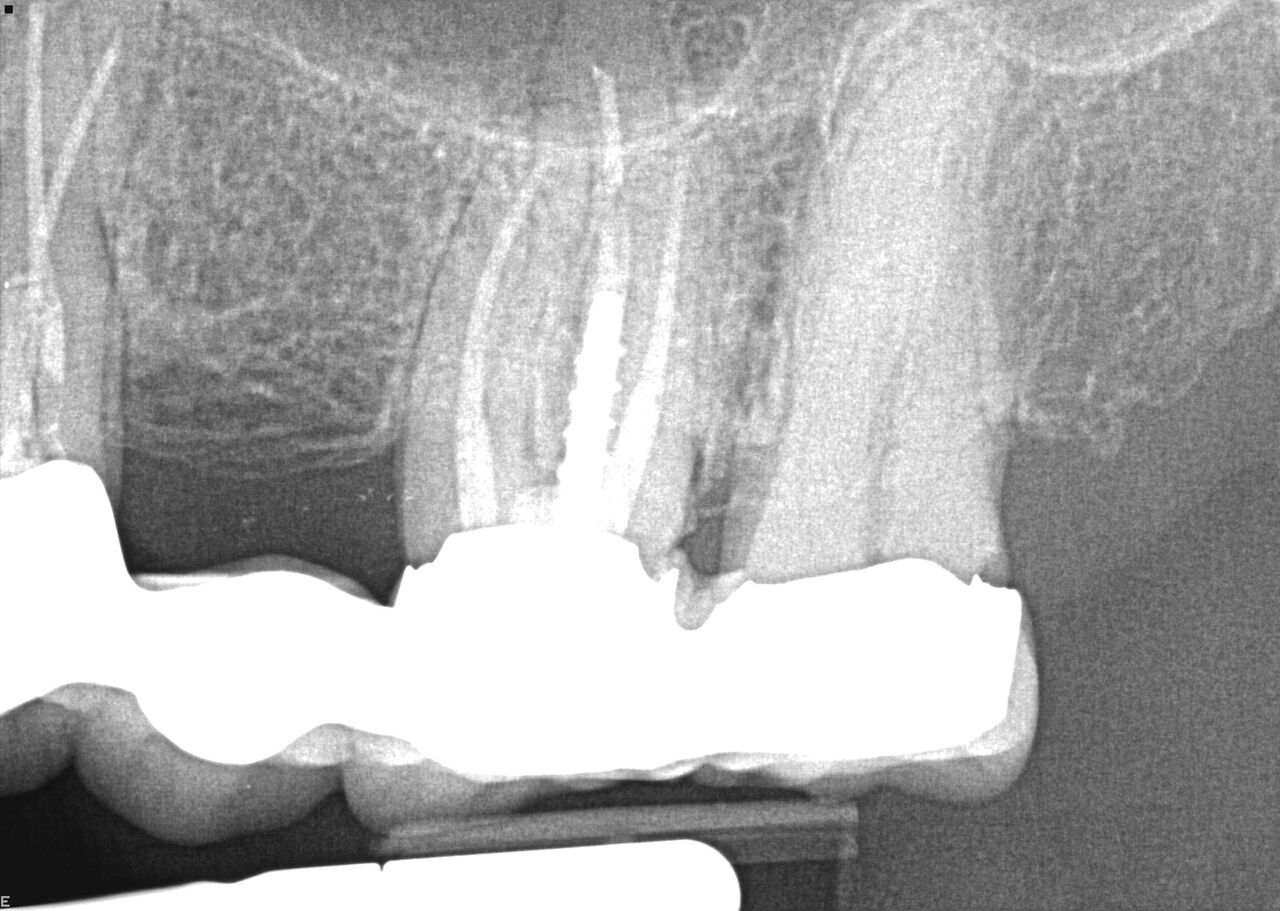

(24.) Radiograph of postoperative individual crowns on Nos. 6 through 10.

Figure 24

(25.) Radiograph of postoperative individual crowns on Nos. 6 through 10.

Figure 25

A 42-year-old man presented with a very loose bridge on Nos. 6 through 9 with periodontally compromised retainers on Nos. 6 and 9 (Figure 17 through Figure 19), and endodontically involved No. 10 with a calcified canal. Teeth Nos. 6, 9, and 10 were extracted, the sockets fully debrided, and pontic soft tissue on Nos. 7 and 8 sculpted to be symmetrical in soft tissue contour with the contralateral lateral incisor and central incisor locations. Implants were secured in position Nos. 6 through 10 (Figure 20) in excess of 45 Ncm, the bone was milled to provide unimpeded seating of temporary abutments, and temporary crowns were fabricated chairside and adjusted to be out of occlusion in centric relation and all excursions. The temporary crowns were cemented after extrusion of excess cement extraorally and the patient was prescribed antibiotics, analgesics, and instructed in postoperative care particular to immediately provisionally restored implants. At 6 months, integration was confirmed (Figure 20 through Figure 23) and after placement of scanning abutments, the implants and soft tissues were scanned. Final crowns were fabricated from the scanned images and were cemented after extrusion of excess cement extraorally (Figure 24 through Figure 26), and oral hygiene procedures were reviewed.